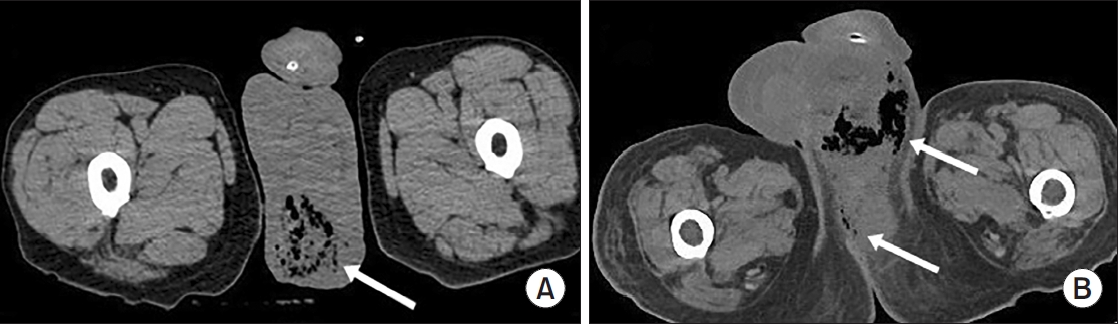

A total of 84 patients were included in this study. The mean age was 58.1±15.9 years, and 95.2% were male. The most common comorbidity was diabetes mellitus (42.9%), followed by hypertension (36.9%). Sepsis occurred in 38.1%, ICU care was required in 42.9%. Among patients who required ICU care, the mean ICU stay was 8.0 days. The overall in-hospital mortality rate was 14.3% (Table 1). The most frequent organisms from abscess cultures were E. coli (29.8%) and K. pneumoniae (19.0%), with Staphylococcus spp. and other organisms comprising 10.7% and 33.3%, respectively (Supplementary Fig. 1). Representative CT images from 2 illustrative cases are shown in Fig. 1.

Fig. 1.

Representative computed tomography findings in patients with Fournier gangrene. Arrows indicate affected areas in each image. (A) Subcutaneous gas and fascial thickening of the perineum. (B) Extensive gas formation and soft-tissue swelling involving the scrotum and extending into the perineum.